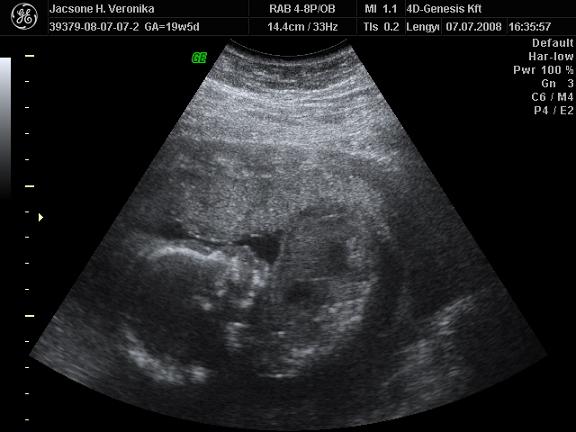

Nos nekem horrorisztikus 4 napom volt: kezdődött csütörtökön, amit írtam, hogy 3.30 óta fentvoltam, aztán mentem 4 D-re, 20 km-es út 1 óra 50 percig tartott kocsival, elkéstem, Glória végig aludt, a doki mondta, hogy kevesebb a magzatvíz, mint kéne, még mindig nem fordult meg Glóri, aztán este mentünk Balcsira, 140 km/órás sebességnél a sztrádán leállt a kocsi, felforrt a víz.... be kellett vontatni, halálfélelmem volt, szakadt az eső...temérdek pénz lesz megjavítattni, a kocsit lent kellett hagyni, pénteken vissza is jöttünk vonattal :evil: Mára sikerült kipihennem a traumákat...

Most vessetek meg de ez nekem nem volt elég és így elmentem a genesisbe és ott a csajszi annyira korrektül megnézte tetőtől talpig a manócskámat hogy még a szájpadlását is láttuk meg mindenét. Szóval tényleg rendben a babó. És mondta hogy nem azért nem látni rendesen mert vastag a hasfalam hanem mert még minidg hátrahajló a méhem eléggé plusz a gyerek lent fexik totáll a medencémbe.

És még anniyt hogy nem láttunk kukacot. :wink: :wink: :wink: :wink: